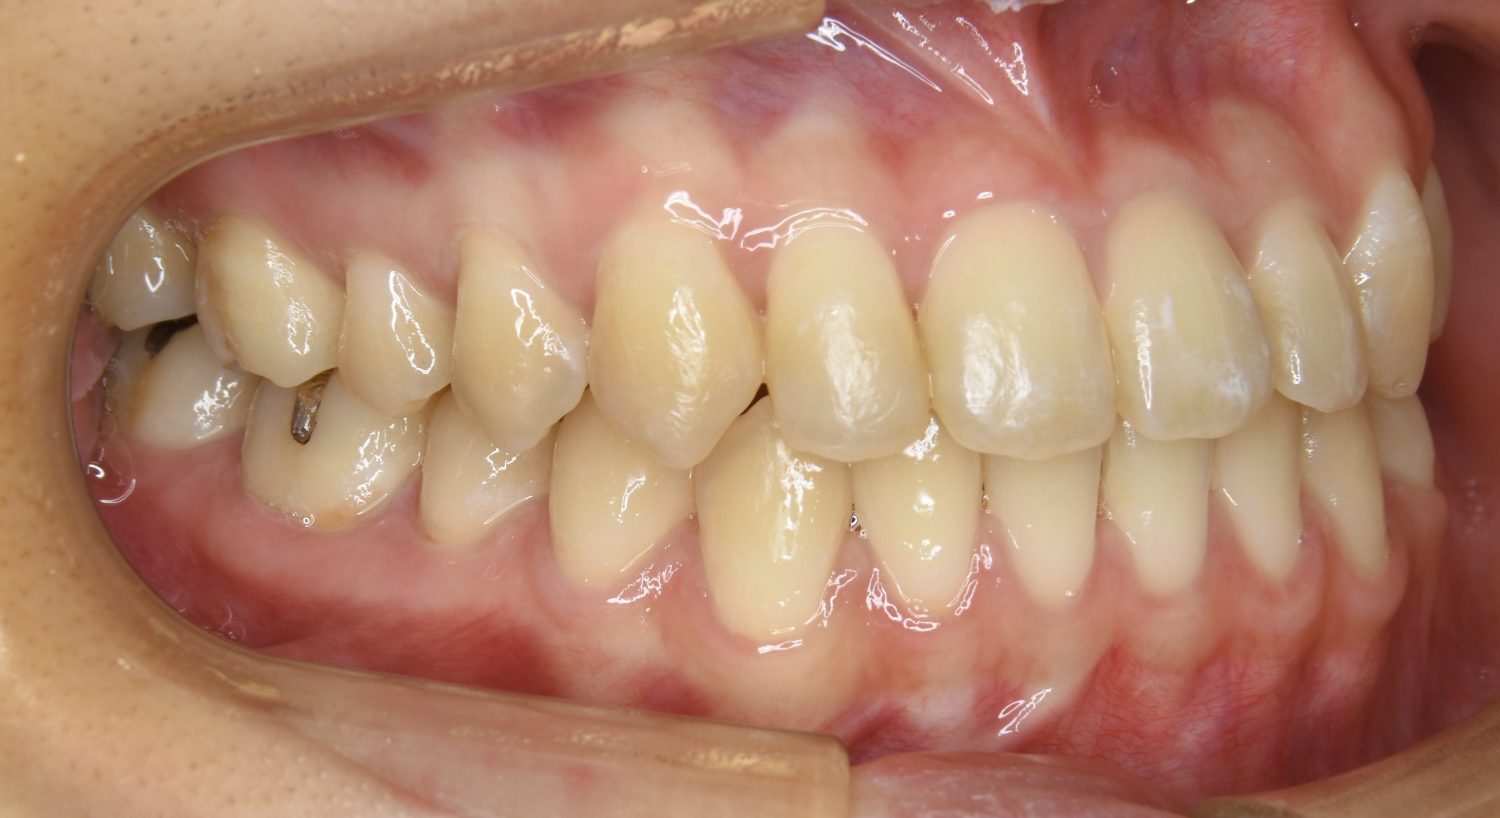

前歯部開咬の症例紹介②

Before

主訴

前歯で物が噛めない

治療内容

上下ラビアルブラケット(唇側装置)に矯正用アンカースクリューを併用し非抜歯で治療を行いました。

上下の前歯が開いており前歯では全く噛めていない状態でした。臼歯の圧下を行うことで機能面のみでなく審美面も改善しました。